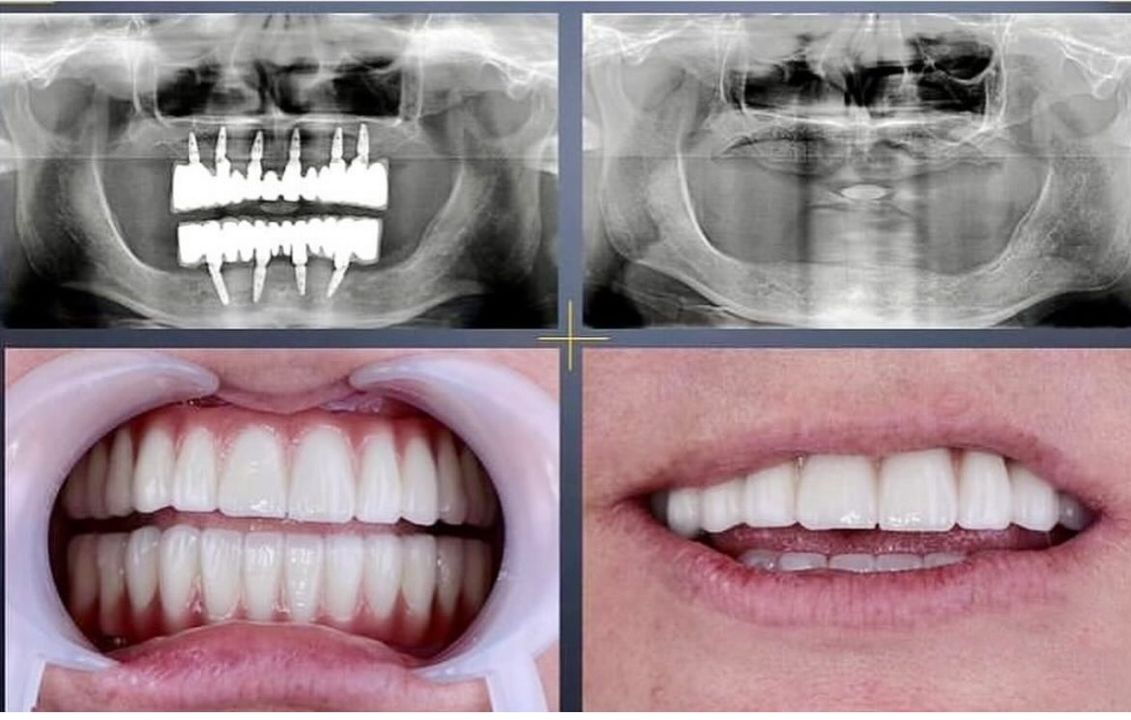

İmplant tedavisi

İmplant Tedavisi ile Kalıcı ve Güvenli Çözüm

İmplant tedavisi, eksik dişlerin yerine çene kemiğine yerleştirilen titanyum vidalar sayesinde doğal diş fonksiyonunu yeniden kazandıran modern ve kalıcı bir yöntemdir. Kemikle biyolojik uyum sağlayan implantlar, üzerine yerleştirilen protezlerle birlikte hem estetik hem de fonksiyonel açıdan güçlü bir sonuç sunar.

Eksik dişler zamanla kemik kaybına ve çevre dişlerde bozulmaya neden olabilir. İmplant tedavisi, kemik yapısını destekleyerek bu sürecin önüne geçmeye yardımcı olur. Sağlam bir temel, sağlıklı ve özgüvenli bir gülüş demektir.

İmplant Tedavileri

• Dental implant uygulamaları

• İmplant üstü sabit protezler

• İmplant üstü hareketli protezler

• All-on-4 ve All-on-6 tedavi sistemleri